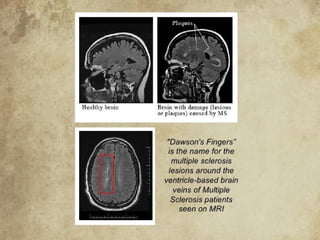

MULTIPLE SCLEROSIS